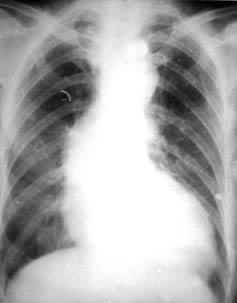

(2)梅毒性主动脉瓣关闭不全。此型在梅毒性心脏病中约占90%,早期可无症状,以后可引起心绞痛,病情进展多较快,晚期多有心力衰竭。病人心界向左下扩大。胸骨右缘第 2肋间或胸骨左缘第3、4肋间有收缩期及舒张期吹风样杂音。舒张期杂音较响,向心尖及腋部传导。约有 5%患者在心尖部可听到舒张期隆隆样杂音是由于经主动脉瓣返流的血液限制了二尖瓣开放所致。如返流量较大,则脉压增大并出现毛细血管搏动、水冲脉及枪击音等体征。X射线检查可见升主动脉增宽,心腰凹陷,左室增大(见图)。对本型的治疗应注意防治心力衰竭及感染性心内膜炎。也可作人工瓣膜置换术,但效果多不甚理想。已发生心力衰竭的病人预后较差,多在2~3年内死亡。